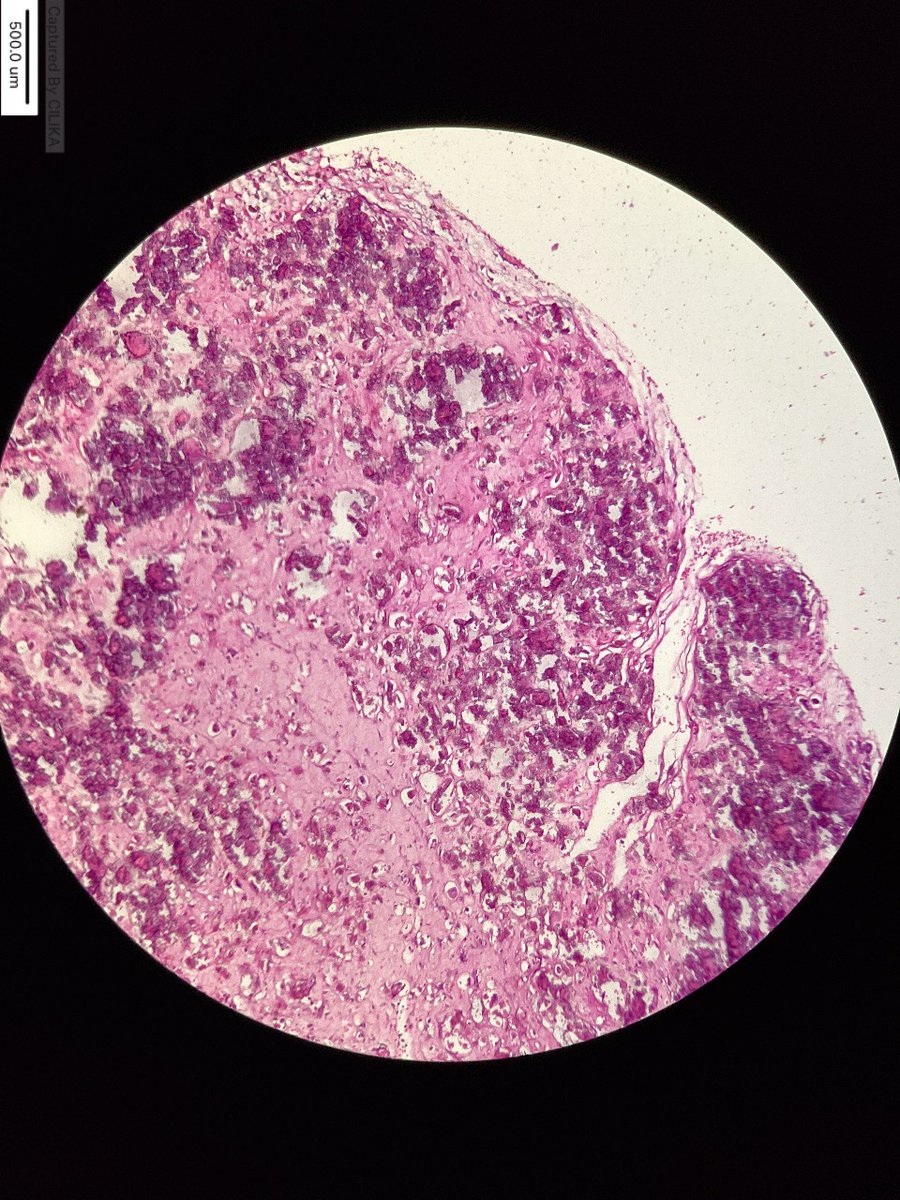

#MTPathUnknown #269

Another finding in decomposed body.

Two images--first is lower power, second is higher power (and maybe a little easier).

Hint: common finding at autopsy

What is the most likely diagnosis?